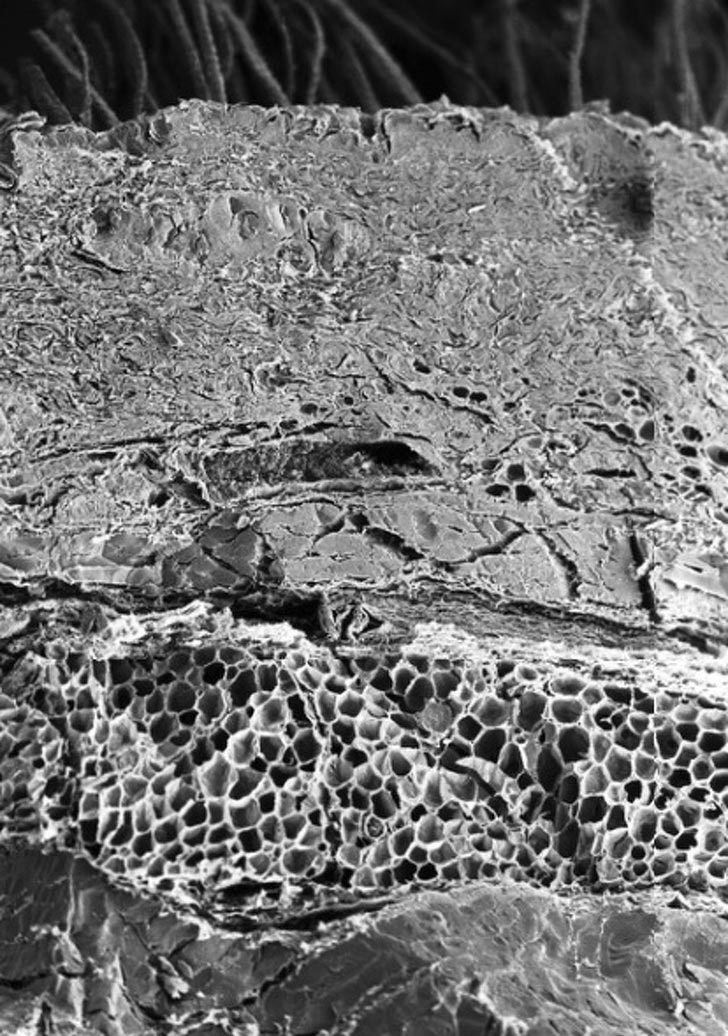

Кость